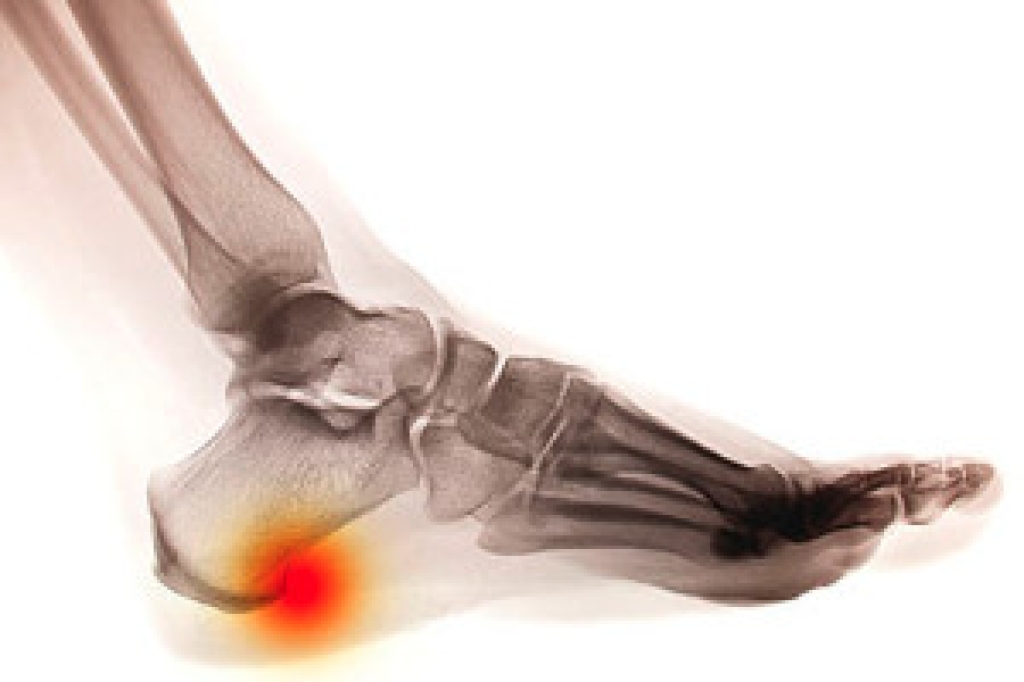

Plantar fasciitis – Pressure and stress that is placed on muscles, joints, and tendons can trigger plantar fasciitis, which is an inflammation of tissue that forms along the bottom of the foot.